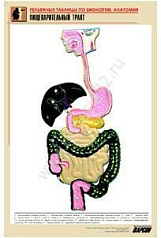

8. Пищеварительный тракт;